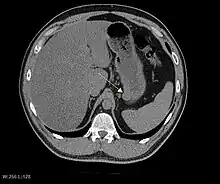

CT scanning is often undertaken (see the radiology section).

Imaging

The purpose of radiologic imaging is to locate the lesion, evaluate for signs of invasion and detect metastasis. Features of GIST vary depending on tumor size and organ of origin. The diameter can range from a few millimeters to more than 30 cm. Larger tumors usually cause symptoms in contrast to those found incidentally which tend to be smaller and have better prognosis.[4][13] Large tumors tend to exhibit malignant behavior but small GISTs may also demonstrate clinically aggressive behavior.[14]

Barium fluoroscopic examinations and CT are commonly used to evaluate the patient with abdominal complaints. Barium swallow images show abnormalities in 80% of GIST cases.[14] However, some GISTs may be located entirely outside the lumen of the bowel and will not be appreciated with a barium swallow. Even in cases when the barium swallow is abnormal, an MRI or CT scan must follow since it is impossible to evaluate abdominal cavities and other abdominal organs with a barium swallow alone. In a CT scan, abnormalities may be seen in 87% of patients and it should be made with both oral and intravenous contrast.[14] Among imaging studies, MRI has the best tissue contrast, which aids in the identification of masses within the GI tract (intramural masses). Intravenous contrast material is needed to evaluate lesion vascularity.

Preferred imaging modalities in the evaluation of GISTs are CT and MRI,[16]: 20–21 and, in selected situations, endoscopic ultrasound. CT advantages include its ability to demonstrate evidence of nearby organ invasion, ascites, and metastases. The ability of an MRI to produce images in multiple planes is helpful in determining the bowel as the organ of origin (which is difficult when the tumor is very large), facilitating diagnosis.

Large GISTs

As the tumor grows it may project outside the bowel (exophytic growth) and/or inside the bowel (intraluminal growth), but they most commonly grow exophytically such that the bulk of the tumor projects into the abdominal cavity. If the tumor outstrips its blood supply, it can necrose internally, creating a central fluid-filled cavity with bleeding and cavitations that can eventually ulcerate and communicate into the lumen of the bowel. In that case, barium swallow may show an air, air-fluid levels or oral contrast media accumulation within these areas.[14][17] Mucosal ulcerations may also be present. In contrast-enhanced CT images, large GISTs appear as heterogeneous masses due to areas of living tumor cells surrounding bleeding, necrosis or cysts, which is radiographically seen as a peripheral enhancement pattern with a low attenuation center.[13] In MRI studies, the degree of necrosis and bleeding affects the signal intensity pattern. Areas of bleeding within the tumor will vary its signal intensity depending on how long ago the bleeding occurred. The solid portions of the tumor are typically low signal intensity on T1-weighted images, are high signal intensity on T2-weighted images and enhanced after administration of gadolinium. Signal-intensity voids are present if there is gas within areas of necrotic tumor.[15][18][19]

Features of malignancy

Malignancy is characterized by local invasion and metastases, usually to the liver, omentum and peritoneum. However, cases of metastases to bone, pleura, lungs and retroperitoneum have been seen. In distinction to gastric adenocarcinoma or gastric/small bowel lymphoma, malignant lymphadenopathy (swollen lymph nodes) is uncommon (<10%) and thus imaging usually shows absence of lymph node enlargement.[13] If metastases are not present, other radiologic features suggesting malignancy include: size (>5 cm), heterogeneous enhancement after contrast administration, and ulcerations.[4][13][20] Also, overtly malignant behavior (in distinction to malignant potential of lesser degree) is less commonly seen in gastric tumors, with a ratio of behaviorally benign to overtly malignant of 3-5:1.[4] Even if radiographic malignant features are present, these findings may also represent other tumors and definitive diagnosis must be made immunochemically.